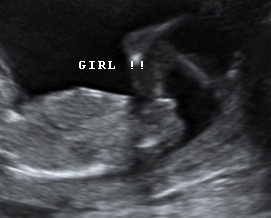

I had a private scan the other day and it was confirmed I'm having a girl!! The nub pics i posted generated 50/50 guesses. Thank you all for guessing! Attachment 5921 Here are the nubs at 12 weeks 2 days for reference. Attachment 5918Attachment 5919